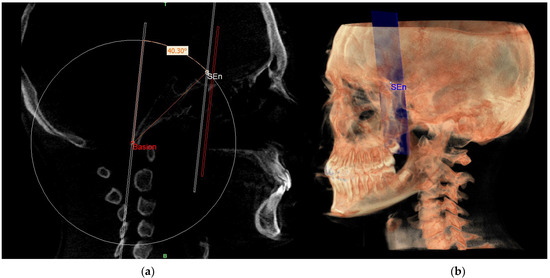

| SEn | SE neutral: the point of a circumference with the center in Ar and the radius equal to the MCF, in which an angle of the skull base equal to 40.3° is obtained |

| PMn | PM neutral: the line parallel to the PM forming at the point SEn an ideal angle of 40.3° with the MCFn |

| MCFn | MCF neutral, Ar—Sen |

| SE neutral (SEn) | / | Point of a circumference with center in Ba and radius equal to MCFx, in which an angle of the skull base equal to 40.3° is obtained | / |

| Right SE neutral (rSEn) | / | Point taken arbitrarily on the right side of the SEn on the same arc of circumference | / |

| Left SE neutral (lSEn) | / | Point taken arbitrarily on the left side of the SEn on the same arc of circumference | / |

| Middle point MCF (MCFx) | / | Point of intersection between the plane on which the Ba lies and a line joining the left and right MCF | / |

| MCF neutral (MCFn) | Plane passing through the Ba, rSEn and lSEn which forms an angle of 40.3° with the PMn at the SEn point |

| PM neutral (PMn) | Plane parallel to the PM such as to form an ideal angle of 40.3° with the MCFn at the SEn point |